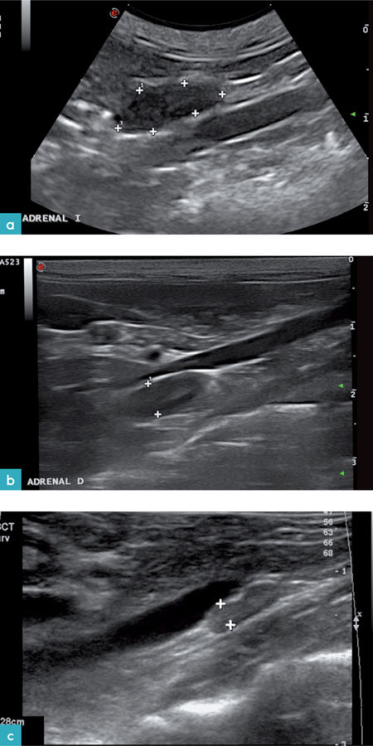

猫的肾上腺是边界清晰,低回声的双叶形结构,外围由高回声的脂肪包裹。一些动物的肾上腺实质呈现两种不同回声,中心高回声,外周区域低回声。目前尚不清楚高低回声的两个区域是否是与皮质髓质分界有关。猫的肾上腺是中心呈低回声,外周呈高回声。

两侧肾上腺通常大小和形状都差不多,呈椭圆形或者豆状。

一些猫的肾上腺内部可以看到高回声伴声影区域。30%健康猫的肾上腺内可以观察到钙化灶。有些人在健康猫单侧或双侧的肾上腺上发现高回声但无声影区域,有可能是因为此处的钙化灶未产生声影,脂肪沉积或局部的血肿(图.3.视频4)。